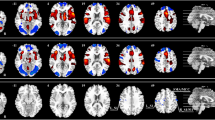

The univariate analysis repeated on our control nociceptive condition, i.e., cold pain, yielded similar results as in the heat paradigm. Significant brain activation was detected in response to high intensity cold stimuli: increased activation was detected in areas including the putamen, the caudate nucleus, the secondary somatosensory cortex, the insula, the anterior cingulate cortex, and the dorsolateral prefrontal cortex, while decreased activation was detected in areas including the amygdala and hippocampus, the primary somatosensory cortex, the posterior cingulate cortex and the precuneus. However, no relationship with individual pain intensity ratings could be identified (Fig. 3, Supplementary Tables 4 and 5). Thus, the findings from heat pain generalized to cold pain.

A Ratings of pain intensity in response to high intensity cold stimuli ranged from 0 to 6.82. Mean and standard error represented by the bar plot. n = 73 participants. B Effect of high intensity cold stimulation on brain activation. Areas of increased activation included the putamen (Put), caudate nucleus (Cau), secondary somatosensory cortex (SII), insula (Ins), anterior cingulate cortex (ACC), and dorsolateral prefrontal cortex (DLPFC). Areas of decreased activation included bilateral amygdala and hippocampus (Amy/Hippo), primary somatosensory cortex (SI), posterior cingulate cortex (PCC) and precuneus (Prec). C There was no relationship between perceived pain intensity and brain activation associated with high intensity cold stimulation. Source data are provided as an xlsx Source Data file and activation maps are available on Github.